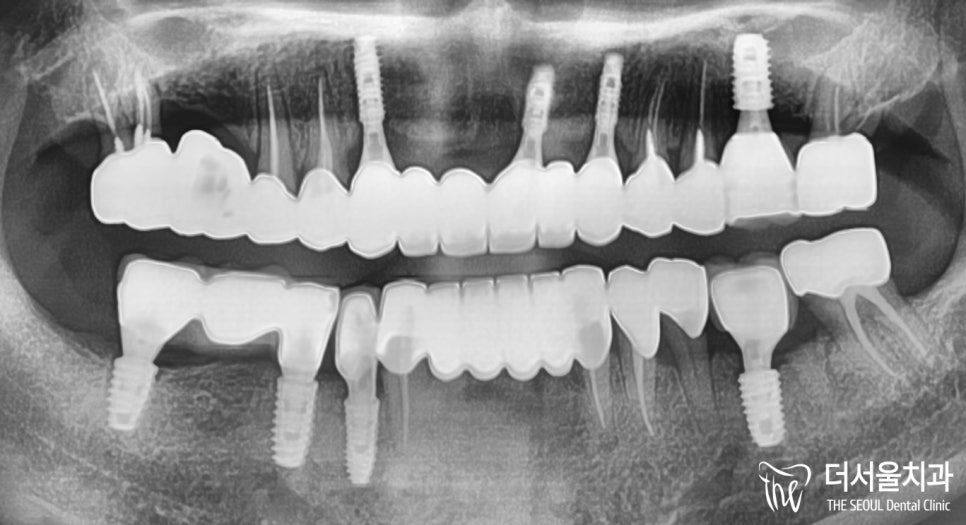

『결과』

우선 파노라마 촬영본을 보여드리는데요.

성남 가천대역치과 첫 내원 때와 달리 깔끔히 정리되었죠?

앞니 치아 깨짐 및 부러짐으로 인한

흔들림이 없어졌기에

환자분 역시 많이 편해졌다며

결과에 만족스럽다고 말씀하셨습니다.

이제 실제 결과물을 봐야겠죠?

실제 구강 내 임플란트 식립 상태인데요.

깔끔히 정리가 잘 되었죠?

주변에 있는 치아들과 비교를 해서

자연스럽게 연출될 수 있도록

보철 제작에 심혈을 기울였습니다.